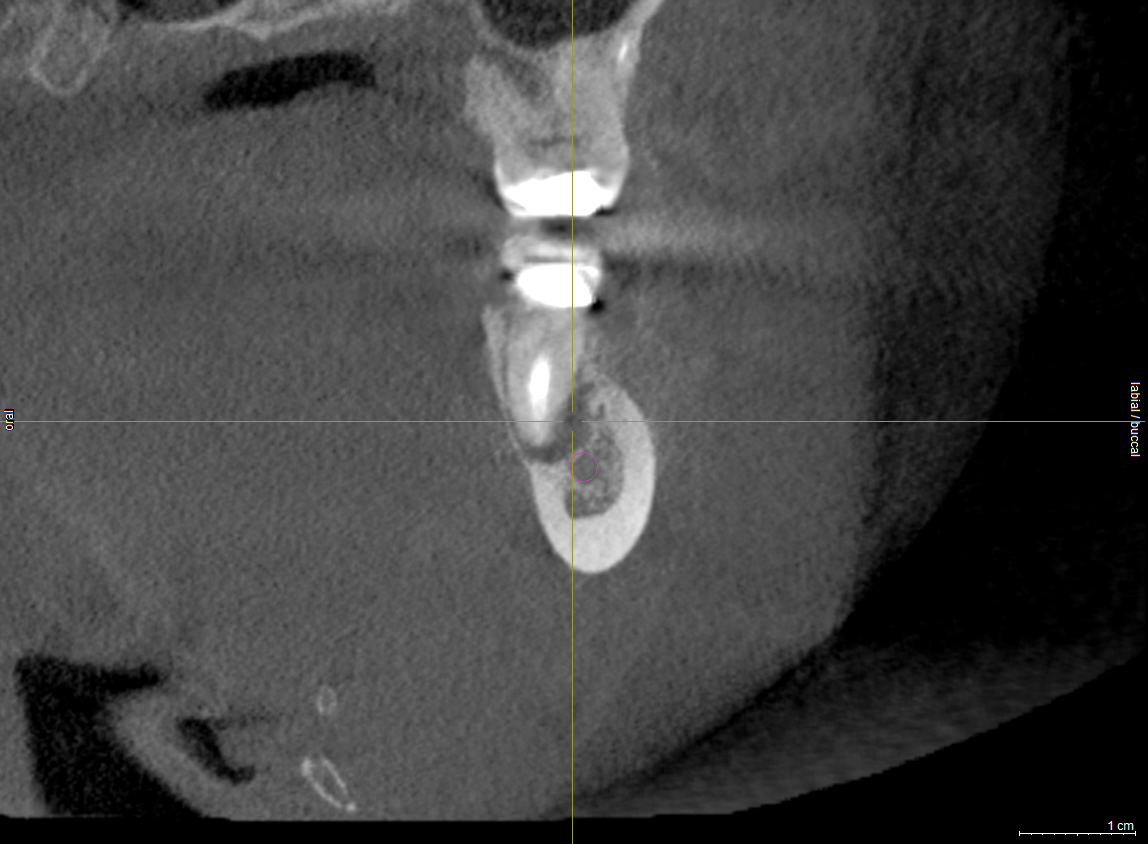

To ensure correct implant placement with the least amount of complications, preoperative planning is necessary. Avoiding nerve injuries starts with proper patient selection, which is done in association with good diagnostics. If it is believed that a computerized tomography (CT) scan or surgical guide would be beneficial, then it should be utilized. Individuals performing surgeries must confirm the path of the mandibular nerve that may have been outlined on a scan by a radiologist. When placing dental implants, a 2-mm safety zone should be left apical to implants over the IAN to accommodate minor drilling errors and drill lengths should be adjusted to take into account radiographic distortion.19,29 In addition, the 2-mm safety zone may help avoid pressure placed on the nerve due to bone compression when the implant is placed close to the mandibular or mental canals (Figure 1 and Figure 2). If necessary, short implants can be used to remain in the safety zone.30 Clinicians should also be aware that drill markings to denote bur length do not take into consideration the extra length of the tapered drill tip, which can add anywhere from 0.4 mm to 1.5 mm to the actual drill size.19,31 In addition, over the IAN or mental nerve, it is advantageous to use drill stops to avoid over-drilling.19,31 It should be underscored that the thickness or density of the bone surrounding the IAN does not provide substantial resistance to drill penetration and excess force should be avoided when drilling over the IAN.32

Subsequent to nerve injury, the clinician needs to determine if immediate referral is necessary or a pharmacologic approach is warranted or if implant removal or reverse-torquing it a little would best serve a patient. There are diverse opinions in the literature pertaining to when and under what conditions referral to a microsurgeon is needed.58,59 It is generally agreed that if a clinician believes that a nerve has been transected as a result of an implant procedure, immediate referral is warranted.12,51,54,60,61 On the other hand, if a patient manifests neurologic symptoms post-implantation, but the clinician is sure that the drill never entered the mandibular canal, it is possible that postoperative altered sensation is caused by traction of a nerve or an inflammatory process. Then a pharmacologic approach may be warranted.3 A clinician can be almost sure that the drill did not enter the mandibular or mental canal if after each drill, the floor of the osteotomy was checked with an implant probe or if a radiograph clearly depicts the osteotomy terminated several millimeters from the nerve canal. The previous remark is qualified, because there is the remote possibility that some unusual branch of the IAN was present and damaged. From another perspective, a CBCT scan can be ordered to attain an enhanced view of the implant’s relationship to vital structures if a 2-dimensional radiograph was initially used to assess the situation (Figure 1 and Figure 2).

Fig 1. An implant was placed at site No. 30. Immediately after the effect of the local anesthesia subsided the patient complained of paresthesia (no pain) of the mandibular right lip and chin. A periapical radiograph taken at the time of implant placement demonstrated no apparent implant penetration into the inferior alveolar canal.

Figure 1

Fig 2. The implant restoration was completed 10 years ago and the patient has been able to accommodate the altered nerve sensation. Recently, the patient presented at one of the authors’ offices and a CBCT scan was ordered. It demonstrated that the implant at site No. 30 is closer to the inferior alveolar canal than previously envisioned and may be causing compression on the nerve.

Figure 2